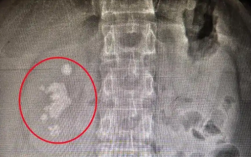

男子查出肾结石未重视拖成大麻烦:发展为铸型结石填满肾脏!

据媒体报道,长沙的向先生十多年前就查出右肾结石,时常感到腰部隐痛,但一直未作处理。直到近期腰部胀痛加剧,影响到日常工作,他才决定就医。没想到检查发现,结石已长成“生姜”形状,几乎填满了整个右肾。...